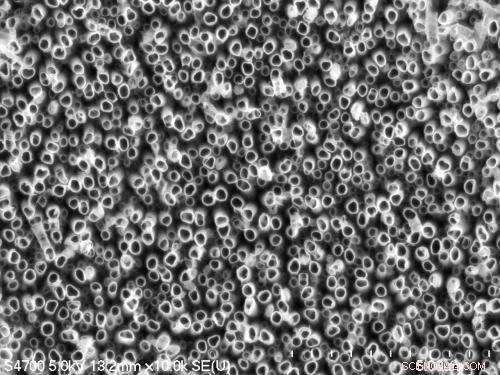

This shows a forest of titanium dioxide nanotubes etched into metallic titanium. The surface holds promise for improving the longevity of dental implants. Credit: Tolou Shokuhfar

Shokuhfar is now working with Cortino Sukotjo, a clinical assistant professor at the University of Illinois at Chicago (UIC) College of Dentistry on a dental implant with a surface made from TiO2 nanotubes, but she has been making and testing them for several years. "We have done toxicity tests on the nanotubes, and not only did they not kill cells, they encouraged growth," she said. She has already demonstrated that bone cells grow more vigorously and adhere better to titanium coated with TiO2 nanotubes than to conventional titanium surfaces. That could keep more dental implants in place.